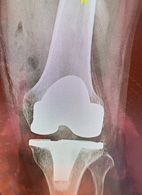

人工關節置換手術為最後的治療方式,但人工關節各廠家的設計理念均不同,效果也不盡相同,近年來高彎曲度之人工膝關節可以有更好的關節活動範圍頗受好評。手術方式也因器械進步傷口變小,關節內肌肉傷害也較少,術後復健快速及滿意度高。電腦輔助導引導航手術更是最近的亮點,可以有更準確的手術導引而減少出血量,減少病患輸血的合併症。

圖三、高彎曲度之人,可以考慮人工關節置換手術